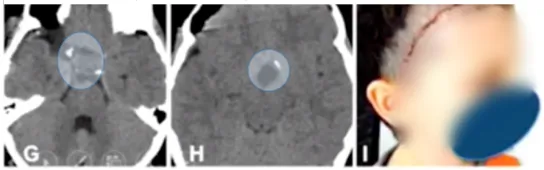

8岁男性患儿因视路-下丘脑胶质瘤导致视力受损就诊。肿瘤位于视路与下丘脑附近,延伸至第三脑室并侵犯梅克尔腔。

术后早期CT扫描显示肿瘤完全切除,未出现局部血肿,患儿无额外并发症。术后两周美容效果满意,面部皮肤切口愈合良好。